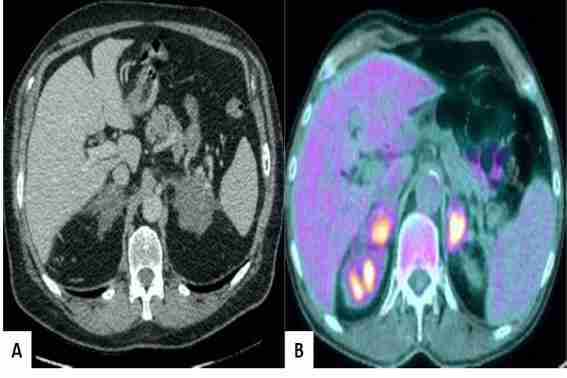

La paciente fue referida al servicio de oncología médica, en el cual fue tratada con 6 sesiones de la combinación rituximab, ciclofosfamida, doxorrubicina, vincristina y prednisona. El tratamiento de sustitución con hidrocortisona fue administrado desde el sexto día luego de cada ciclo de quimioterapia hasta el inicio del siguiente. Las imágenes de tomografía computada sin contraste y por emisión de positrones mostraron reducción significativa del tamaño de los tumores suprarrenales bilaterales previamente descritos, con restauración parcial de la morfología (figura 4). Luego de la sexta sesión de quimioterapia, la paciente mostró excelente respuesta al tratamiento con presencia de tejido de cicatrización en las glándulas suprarrenales residuales y remisión completa de la condición clínica.

Imágenes posteriores al tratamiento con quimioterapia. A) Imagen de tomografía computada que muestra tejido suprarenal cicatrizal con aparente remisión completa del linfoma. B) Imagen de tomografía por emisión de positrones que muestra glándulas suprarrenales metabólicamente activas y de tamaño cercano al normal.